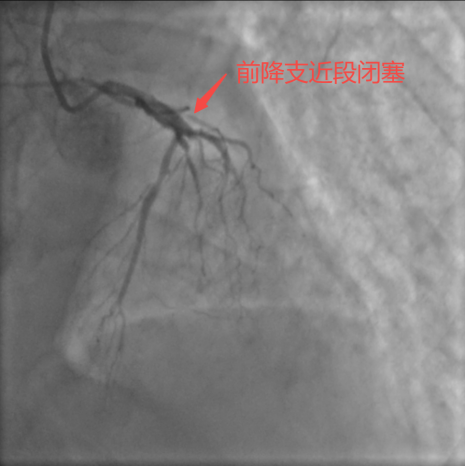

通過電話聯(lián)系上患者家屬并征得同意后,立即上報(bào)醫(yī)院醫(yī)務(wù)部并采取緊急手術(shù)授權(quán)機(jī)制,啟動(dòng)“胸痛中心綠色通道”,由蔣桔泉主任團(tuán)隊(duì)緊急進(jìn)行冠脈介入治療。術(shù)中冠狀動(dòng)脈造影顯示,王先生心臟左前降支(LAD)近段完全閉塞,而且由于患者左回旋支細(xì)小,整個(gè)左心室90%的血液斷供,病情極為兇險(xiǎn),稍有延后極可能猝死。